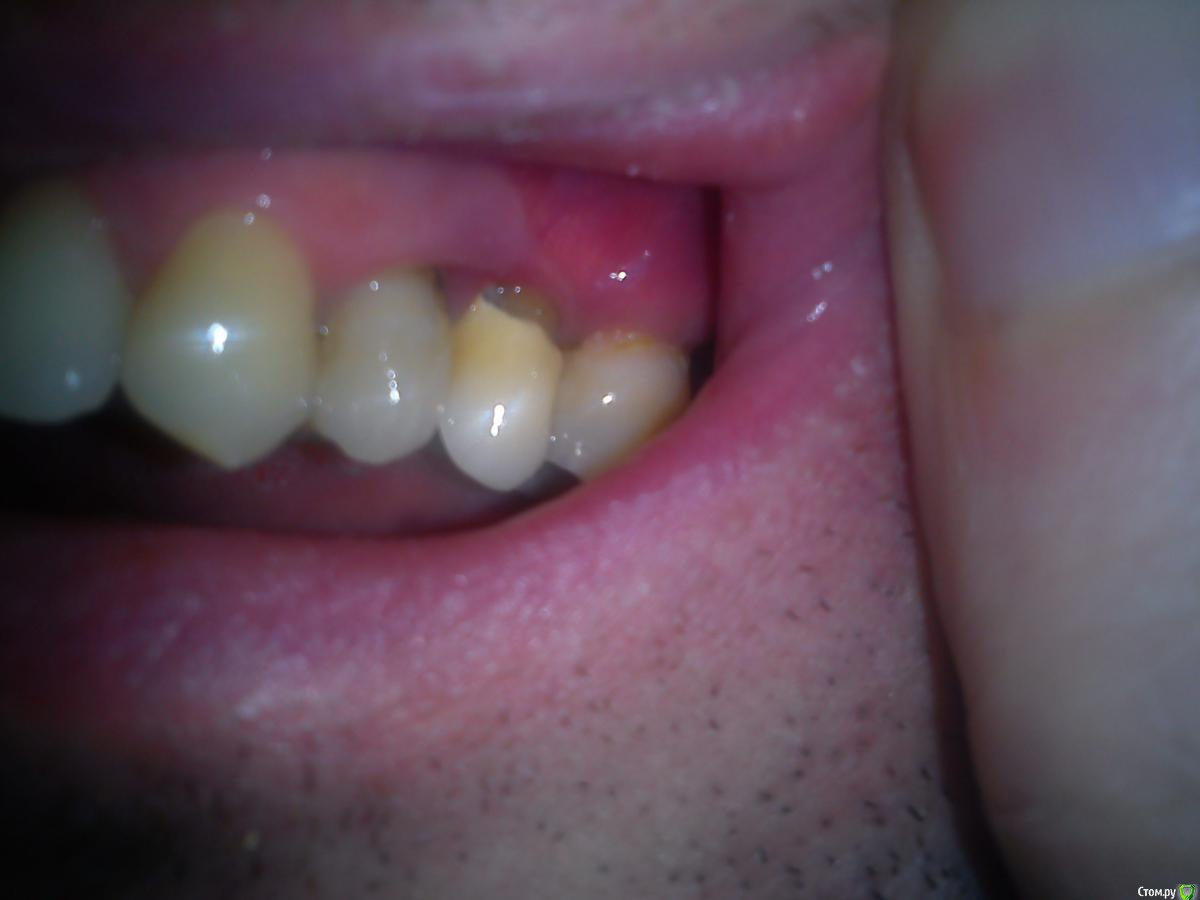

Макс111 Опубликовано 16 декабря, 2015 Поделиться Опубликовано 16 декабря, 2015 Добрый день!По возможности, прошу посмотреть мою КТ. Правда, не разобрался какую именно папку выкладывать, поэтомувот тут ссылка только на папку с файлами с расширением .DCM https://yadi.sk/d/NQrtBNRKmFtRC А вот тут на все содержимое диска вместе с программой для просмотра, на всякий случай:https://yadi.sk/d/O5yoL0QImFu3Y Так же к теме прикрепляю фото 24, 25 с внешней и внутренней стороны, а так же фото ниж ч там где 46 У меня пародонтит, и тд.В целом, вопрос по 24 и 25 зубу, между ними как видно большой карман. 25 это коронка на зубе, десна опустились и она полностью оголилась, видно уже корень , коронка на десной на пару мм. 24 это в общем то пломба огромная на весь зуб.Что можно сделать? Мне предлагают снять коронку, потом сделать лоскутную операцию, в ходе которой подсадить материал для формирования кости, чтоб уменьшить этот карман и потом сделать сделать коронку и на 25 и на 24 тоже коронку одеть.Какое ваше мнение по 24, 25? Как бы вы сделали, в какой очередности?27 и 28 потерял около 9 мес назад, над ними была киста, ее вырезали.А ну и плюс хронический гайморит. Так же прошу посмотреть в низу 46 зуб, можно ли туда вкрутить имплант или предварительно регенерировать кость нужно? каким методом?у 7 ки там такая форма, что между зубами видимо будет пустота? Как с этим бороться? Когда там был зуб так и были и поэтому 46 портился, стояла пломба, но 3 месяца назад он раскололся, сохранить возможности не было, плюс была киста и его пришлось удалить..Стоит ли сразу удалить 48, чтоб он не давил на 47 или можно подождать пока верх сделаю, чтоб было чем есть пока? Спасибо, если кто то посмотрит! Ссылка на комментарий